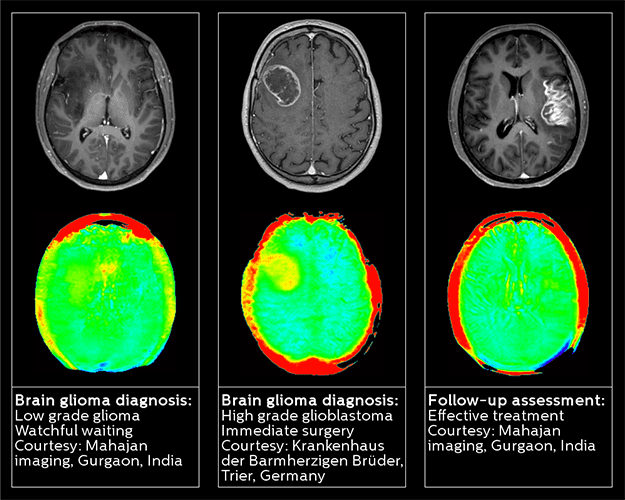

Enhanced diagnostic confidence in Neuro-oncology Establishing the diagnosis of a brain tumor is not always straightforward. MRI is the gold standard but not reliable enough for tumor follow up.1 The presence of contrast enhancement can confuse the diagnosis of malignant brain tumors, and therefore differentiating low- from high-grade gliomas can prove to be a challenge for radiologists. With three out of five radiologists finding brain tumor diagnosis “challenging” to “very challenging,” it’s evident that this is an area of unmet need; there is also a vital demand for methods that can detect response to therapy at early follow-up times.2 Philips 3D APT (Amide Proton Transfer) is a unique, contrast-free, brain MR imaging method, designed to help radiologists differentiate between low-grade and high-grade gliomas. This technology works by using the presence of endogenous cellular proteins to produce an MR signal that directly correlates with cell proliferation, a marker of tumor activity. 1 Neurology. 2002 Sep 24;59(6):947-9. 2 Cancer Manag Res. 2014; 6: 149–170.

By using Philips 3D APT, radiologists can now make a confident diagnosis and more confidently assess the pathway and urgency of a patient’s treatment plan.